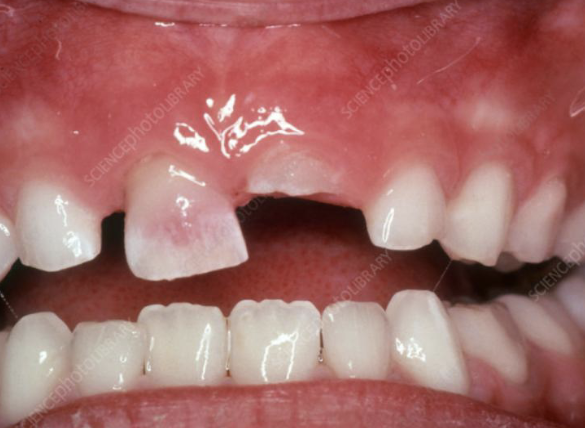

intra-oral presentation of congenital syphilis;1st molars develop irregular nodules of enamel on occlusal surface

mulberry molars

intra-oral presentation of congenital syphilis; “screwdriver” incisor

hutchinson’s incisor